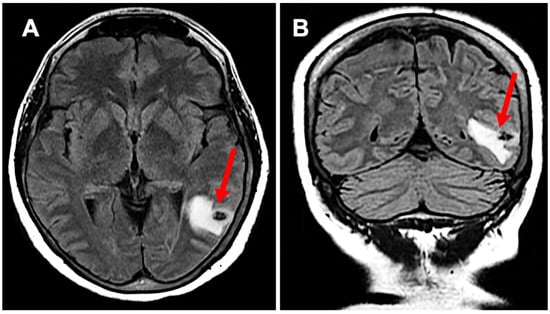

2. Case Presentation